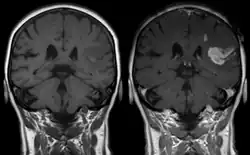

La respuesta de Cushing, también llamada reflejo de Cushing, fenómeno de Cushing o reacción de Cushing, nombrada en honor al neurocirujano estadounidense Harvey Cushing (primero en describir a detalle su fisiopatología),[1][2] es una respuesta fisiológica del sistema nervioso central a la hipertensión intracraneal (HIC) que resulta en la tríada de Cushing: presión sanguínea incrementada, respiración irregular y bradicardia.[3] Normalmente se observa en fases terminales de traumatismos craneoencefálicos agudos y puede indicar herniación cerebral inminente. También se puede observar tras la administración intravenosa de adrenalina y fármacos similares.[4]

La tríada de Cushing es uno de los primeros signos de muerte cerebral inminente y va sucedida por «tormentas adrenérgicas».[5] De acuerdo al propio Cushing, el incremento en la presión intracraneal es la causa primaria de esta respuesta.[2] Los incrementos moderados y continuos en la presión craneal permiten que suceda el reflejo. Sin embargo, los aumentos rápidos no dan el tiempo suficiente para que ocurra.[6]